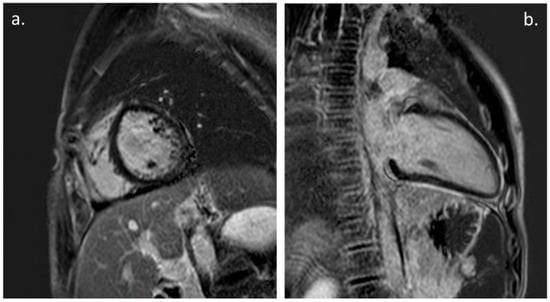

The CMR was performed in 20 patients (31%) during the FU (Figure 2). The time between the onset of the symptoms and the FU CMR was 9.4 +/− 4.6 months. The CMR showed the presence of a myocardial LGE in 10 patients (15% of all of the patients and 50% of all of patients that underwent the CMR) and only one patient showed a persistent mild LV enlargement. No cases of LV dysfunction or myocardial edema were documented at the point of the CMR, and none of the patients showed evidence of a pericardial effusion.

A previous CMR study reported a case series of four children and adolescents with COVID-19, showing that in the acute phase, the presence of a diffuse myocardial oedema with no evidence of an LGE was suggestive of replacement fibrosis or focal necrosis. These findings were correlated with post-infectious myocarditis [20]. On the contrary, in our study, the CMR documented the persistence an LGE that was indicative of myocardial scars in 50% of the patients that underwent the CMR at the 1-year-mark of the FU, without there being evidence of the symptoms, an LV dysfunction or arrhythmias. The meaning of these findings and their possible impact on a patient’s long-term outcome is actually unknown. We believe that this could be a reason to continue to conduct the follow-up of this subgroup of patients.

Figure 2. Cardiac Magnetic Resonance: (a). PSIR, short axis. Mild LGE with subepicardial pattern involving LV infero-lateral wall. (b). PSIR, LV 2-chamber. Mild intramyocardial LGE of the mid-basal inferior wall; also note, persistence of mild pericardial LGE.